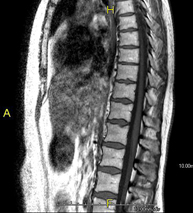

- Thoracic spine MRI

This non-invasive diagnostic procedure uses an electromagnetic field and radio waves (from a transmitter and receiver) to acquire high-definition anatomical images of the thoracic spine. It is a radiation-free procedure. Indicated for: trauma, degenerative problems, hernias, tumours.

- Lumbar spine MRI

This non-invasive diagnostic procedure uses an electromagnetic field and radio waves (from a transmitter and receiver) to acquire high-definition anatomical images of the lumbar and sacral regions. It is a radiation-free procedure. Indicated for: trauma, sciatica, herniated discs, tumours, infections.

- Thoracic + lumbar spine MRI

A non-invasive diagnostic test that involves obtaining high-definition anatomical images of the thoracic and lumbar spine using an electromagnetic field and radio waves (with transmitter and receiver). It is a radiation-free procedure. Indicated for: trauma, spinal degeneration, hernias.